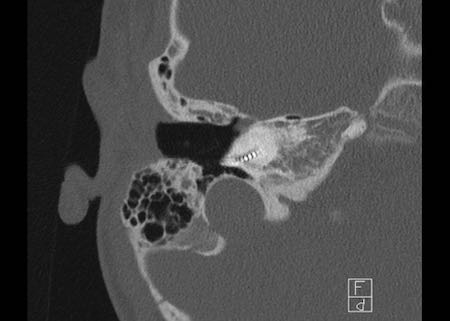

Cholesteatoma

Cholesteatoma: Phụ nữ 20 tuổi với viêm tai tái phát. Mô hạt trên màng nhĩ trái. Khối mô mềm nằm giữa chuỗi xương con và thành nhĩ bên, có hình ảnh bị ăn mòn. Bên phải để so sánh.

Bên trái là hình ảnh của một phụ nữ 20 tuổi với viêm tai tái phát.

Có mô hạt trên màng nhĩ trái.

CT cho thấy một khối mô mềm nằm giữa chuỗi xương con và thành nhĩ bên, có hình ảnh bị ăn mòn.

Điều này ủng hộ chẩn đoán cholesteatoma.

Phụ nữ 20 tuổi với viêm tai tái phát. Mô hạt trên màng nhĩ trái. Khối mô mềm nằm giữa chuỗi xương con và thành nhĩ bên, có hình ảnh bị ăn mòn. Bên phải để so sánh.

Bên trái là các hình ảnh mặt phẳng coronal của cùng bệnh nhân trên.

Lưu ý cholesteatoma đã ăn mòn scutum (mũi tên).